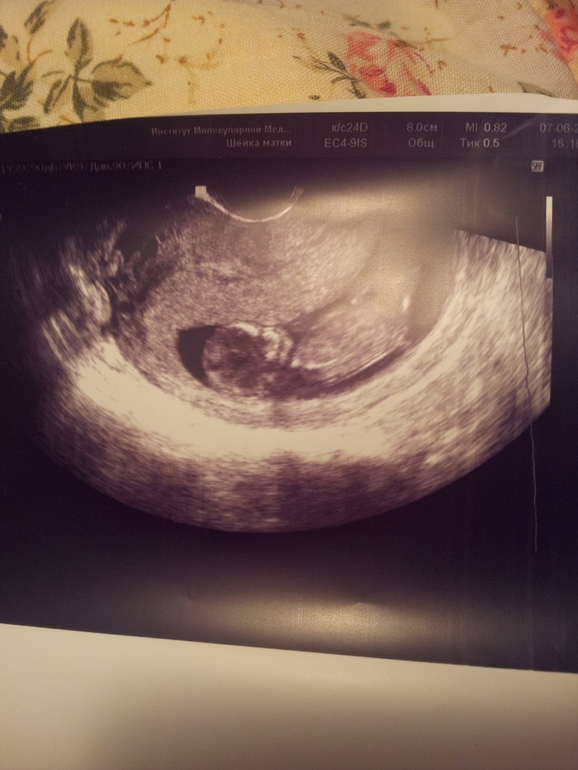

в апреле мы с мужем узнали что беременны. начались приёмы к врачам и шерстка нета на тему беременности. через месяц у меня начался сильнейший токсикоз, мне было вообще не до интернета. 2-3 месяца я лежала пластом, не считая работы, покушать и помыться и т.п. Когда мне стало лучше, и уже "не до работы", я вышла в не паханное поле всемирной паутины)), и набрела на ББ. Почитав, уже через пару тройку дней мне захотелось зарегистрироваться. Вообще я человек не публичный, даже в нете, но ББ располагает)). мне хотелось читать и читать, я находила и по прежнему нахожу ответы на массу вопросов. испытываю чувство огромной благодарности к мирозданию и основоположникам за создание столь полезного и уютного "уголка". Каждый день читаю ленту друзей. также у меня есть любимые сообщества. а еще ББ помог мне купить коляску)). каждый день из ББ я черпаю очень много полезного. И вообще мне здесь очень тепло и уютно. когда доча часами висела на груди, я висела на ББ)).

здесь нам 3 месяца, только отошла от токса, вешу 58 кг, до Б 63 (сейчас 73) совсем чуток видно животик. щеки впали.